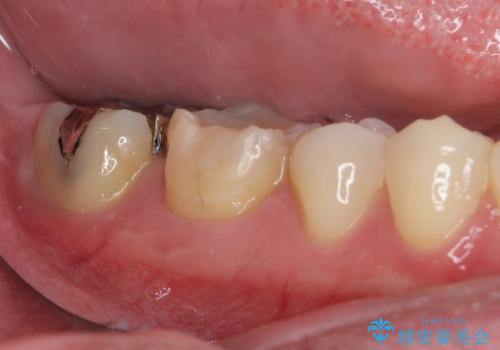

- 右下奥歯の虫歯がしみて痛いとのことで来院された患者様です。

神経近くにまで及ぶ大きな虫歯でしたが、速やかに処置を行い、痛みは即日解消されました。

虫歯が大きかったため、クラウンによる補綴治療が必要になる旨をお伝えしたところ、矯正治療にも興味があるとのことでした。

短期間で手間のかからない方法がご希望でしたので、ワイヤー装置による矯正治療を行うこととし、矯正治療後に右奥2歯をセラミッククラウンにて補綴することとしました。